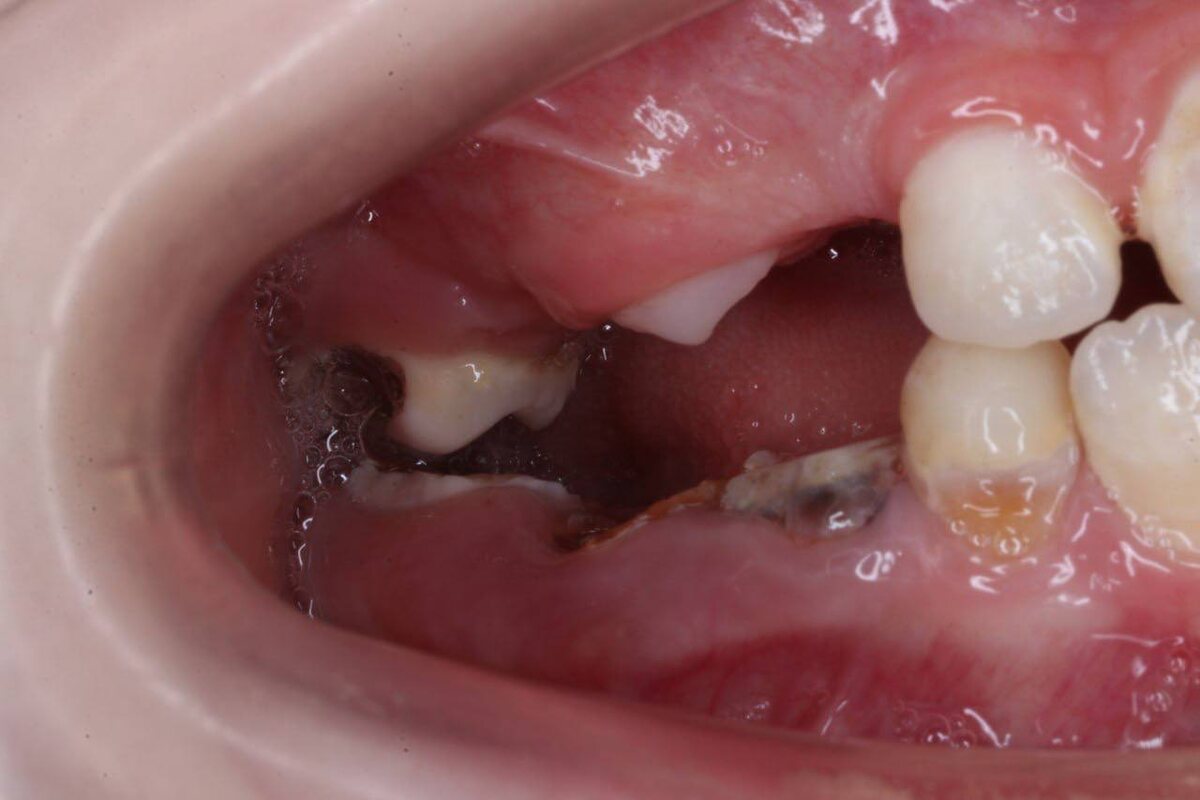

Девочка, 6 лет, негативный опыт, ранее — лечение в наркозе.

Более месяца болит щека слева, несколько клиник рекомендуют удаление 36 и 46 зуба, санация в условиях наркоза.